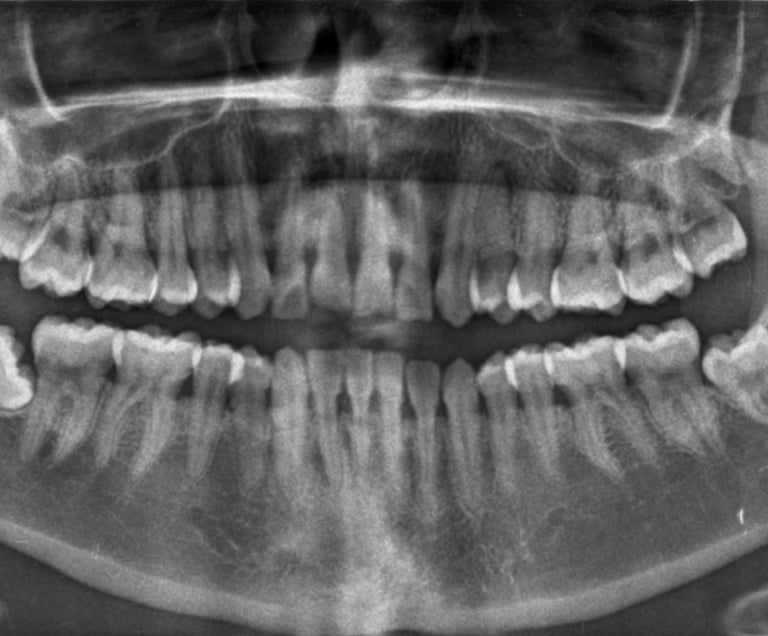

Son muy útiles para detectar fracturas, infecciones, problemas pulmonares o dentales, entre otros.